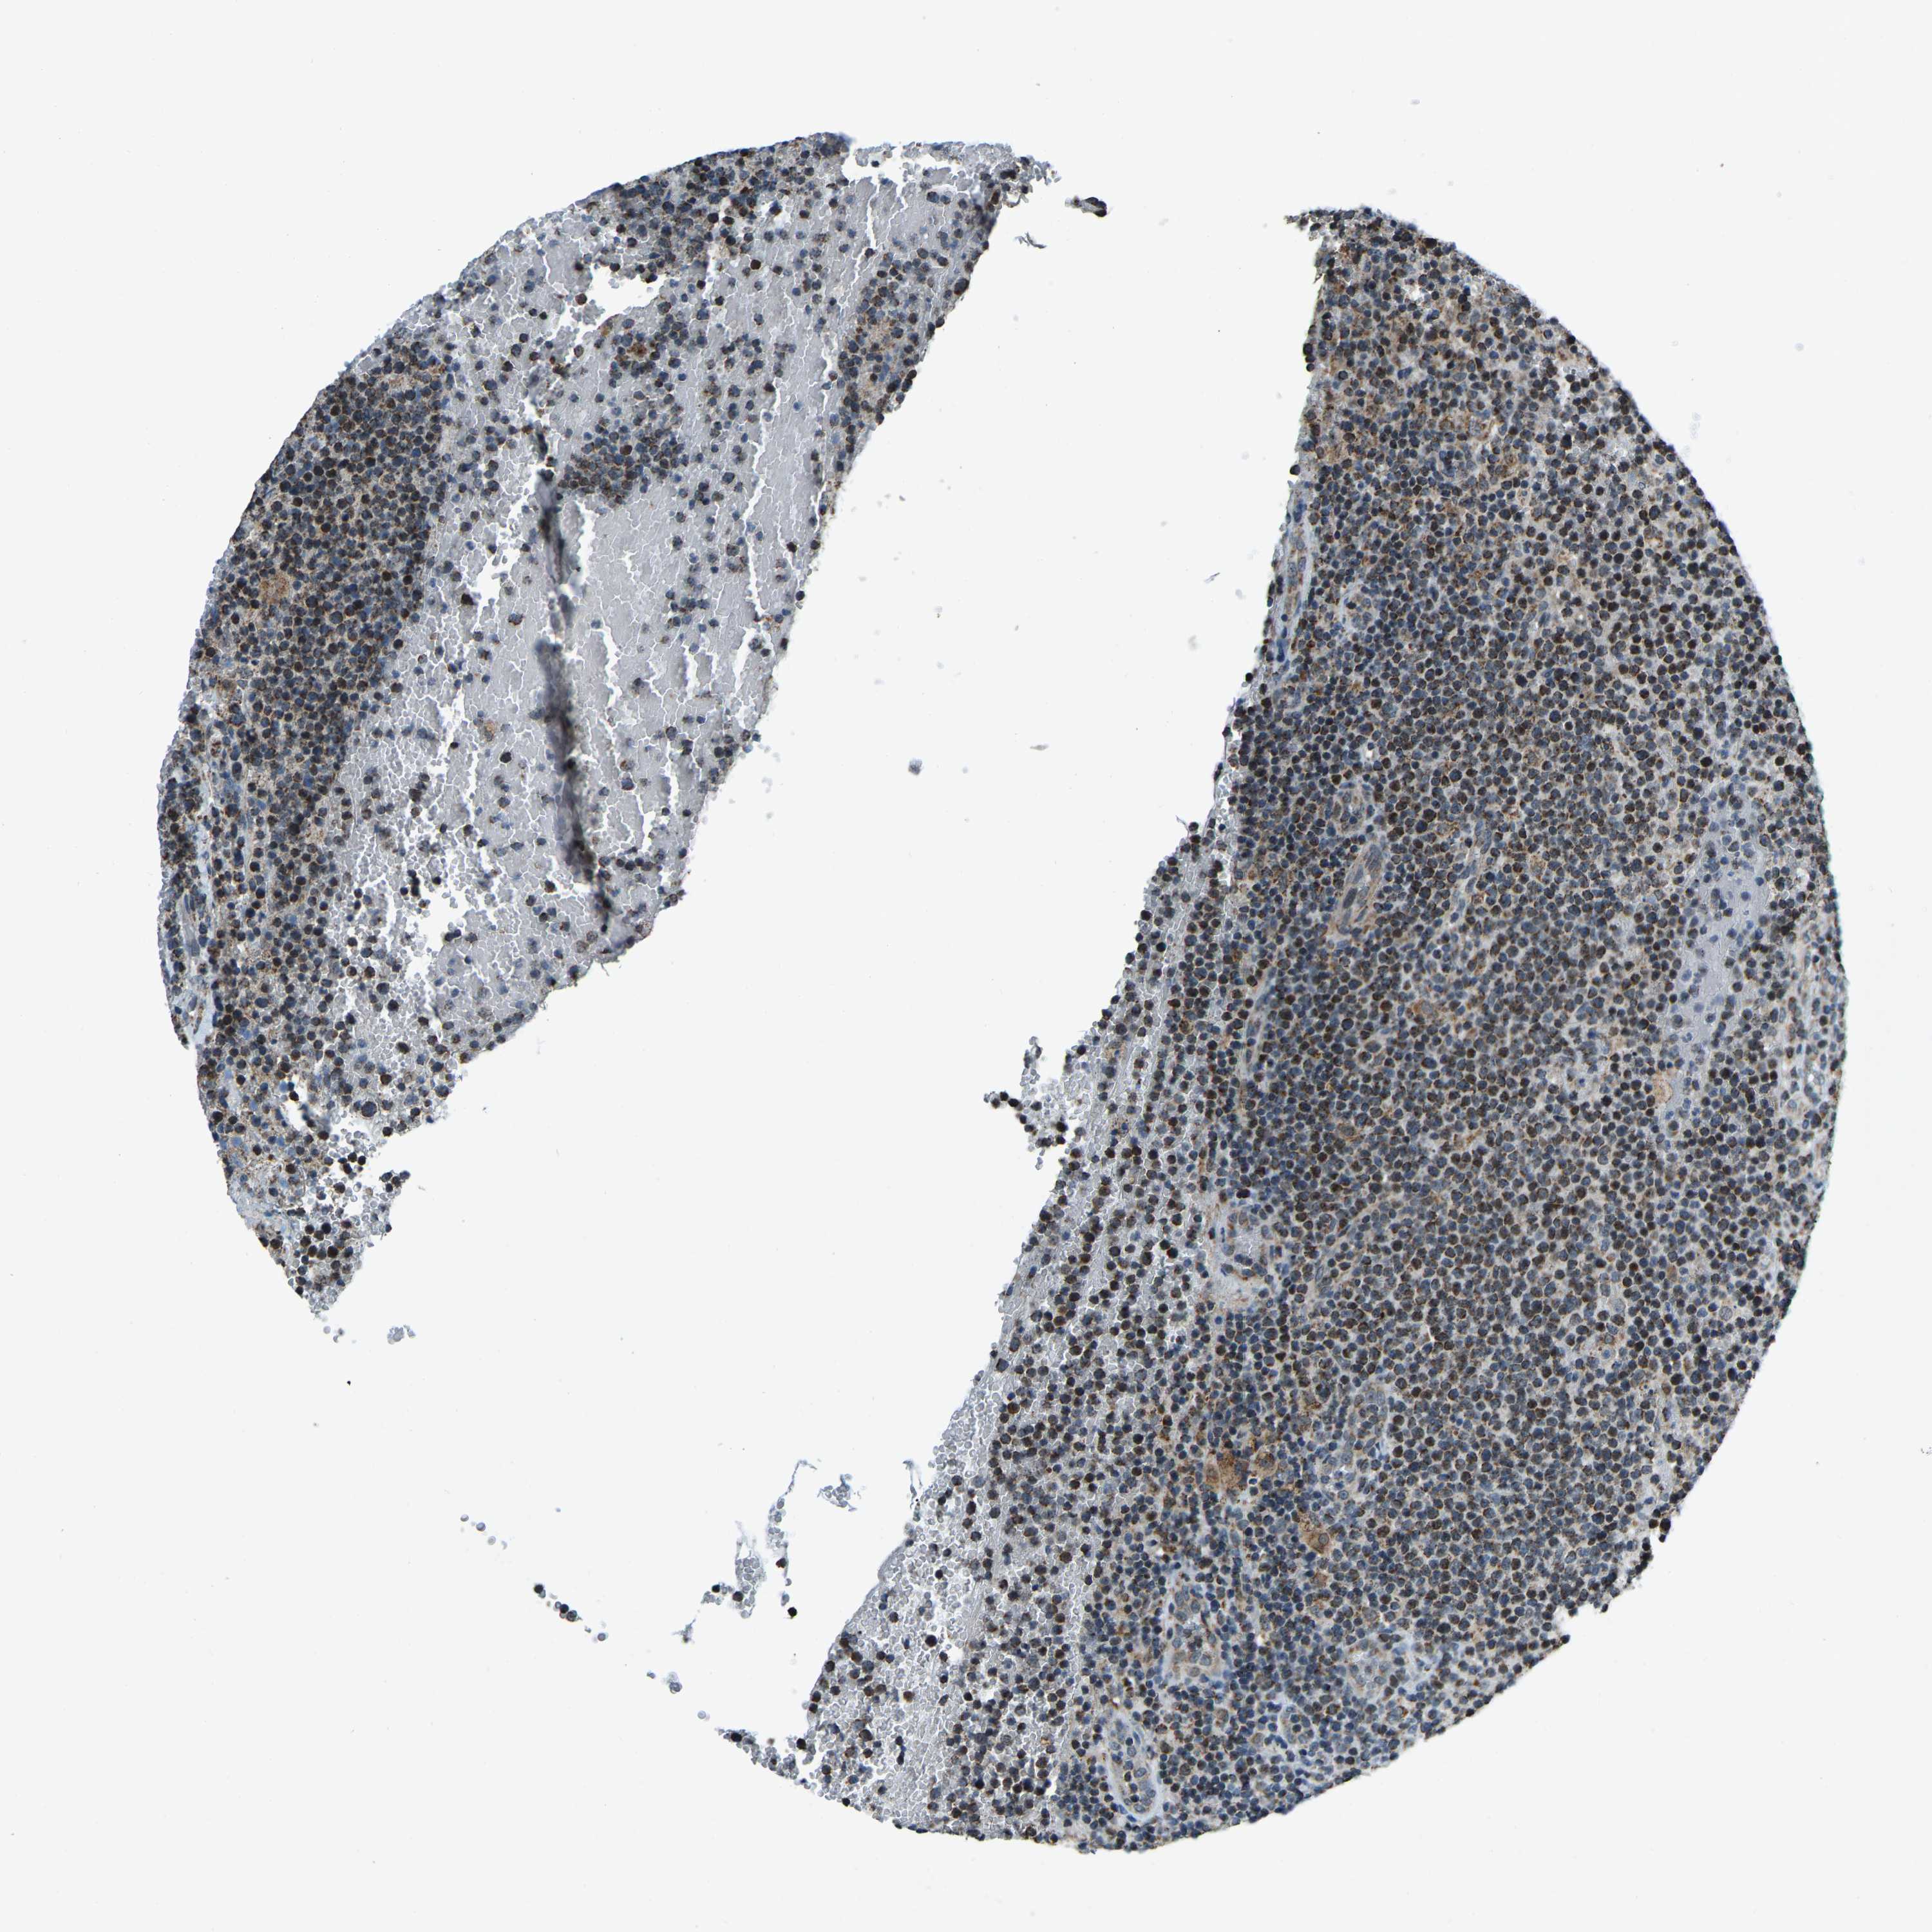

CANCER LYMPHOMA Show tissue menu

LYMPHOMA - Protein expressioni

A mouse-over function shows sample information and annotation data. Click on an image to view it in a full screen mode. Samples can be filtered based on level of antibody staining by selecting one or several of the following categories: high, medium, low and not detected. The assay and annotation is described here.

Each image is clickable and will lead to virtual microscopy that enables deeper exploration of all samples and also displays staining intensity scores, fraction scores and subcellular localization as well as patient and tissue information for each sample.

Antibody HPA019232

Antibody HPA021497

Antibody HPA021768

Hodgkin's disease, NOS

Malignant lymphoma, non-Hodgkin's type, High grade

Malignant lymphoma, non-Hodgkin's type, Low grade